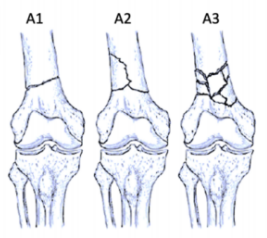

股骨遠(yuǎn)端骨折分型

股骨遠(yuǎn)端骨折可根據(jù)骨折模式、部位和膝關(guān)節(jié)受累情況進(jìn)行分型 ,AO/OTA分型常用于對(duì)這些骨折進(jìn)行分類。在每個(gè)類別中,骨折可根據(jù)復(fù)雜性和移位程度進(jìn)一步分類,對(duì)于與全膝關(guān)節(jié)置換術(shù)(TKA)相關(guān)的假體周圍股骨遠(yuǎn)端骨折,基于骨折移位和TKA股骨假體完整性的Lewis和Rorabeck分型(1997年)是最常用的分型:

A型:關(guān)節(jié)外骨折

不累及關(guān)節(jié)面

B型:部分關(guān)節(jié)內(nèi)骨折

累及部分關(guān)節(jié)面但保持一定的關(guān)節(jié)匹配性

C型:完全關(guān)節(jié)內(nèi)骨折

關(guān)節(jié)面完全破壞